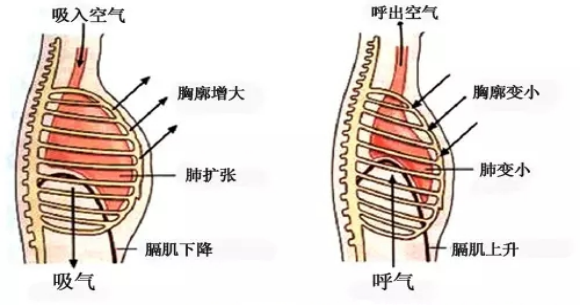

變頻便攜式體外膈肌起搏器是利用功能性電刺激膈神經運動神經元,引起膈肌收縮達到起搏運動,目前唯一一款可以直接作用在膈肌功能康復治療的設備,針對膈肌廢用性病變、萎縮性病變引起的肺功能下降的臨床治療效果確切。

在使用變頻便攜式體外膈肌起搏器治療的過程中,操作者可感覺到治療時患者呼吸深度明顯增加,隨著呼吸深度的增加,患者蓄積在體內的C02得到了更好的排除,同時增加了氧氣的攝入,有效的改善了患者血氣含量,對于患者自主呼吸功能改善效果確切。

1.膈肌刺激可增加膈肌血流量

2.可以改善通氣功能

3.可增加膈肌耐力

4.增加膈肌移動度

8.增加最大通氣量